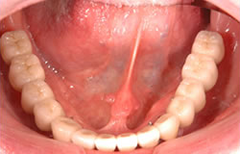

下顎の無歯顎に8本のインプラントを埋入して咬み合わせを作った症例

下顎全顎にインプラント埋入(8本)後、セラミックの歯を装着し、上顎は総義歯をいれた。

約7年経過後も問題はございません。